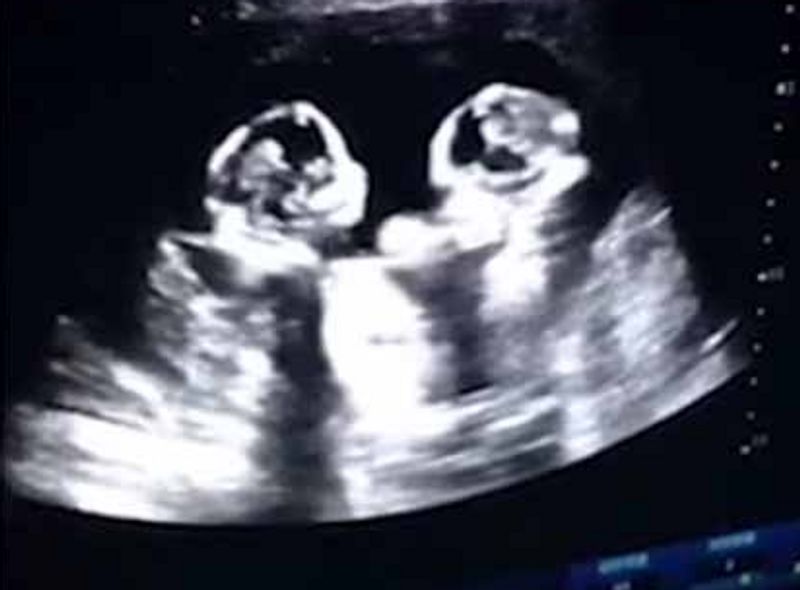

தாயின் வயிற்றுக்குள் இரண்டு குழந்தைகளும் சண்டையிடும் அழகிய காட்சியை ஸ்கேன் செய்யும்போது ரெக்கார்ட் செய்து அதனை சமூக வலைத்தளத்தில் பதிவிட்டு உள்ளனர் பெற்றோர்கள். இந்த வீடியோ அனைவரின் கவனத்தை ஈர்த்துள்ளது.

சீனாவை சேர்ந்த 28 வயதான தாவோ என்பவர் அவருடைய கர்ப்பிணி மனைவியை அருகில் உள்ள மருத்துவமனையில் சிகிச்சைக்காக சேர்த்துள்ளார். அப்போது ஸ்கேன் செய்தபோது கர்ப்பிணியின் வயிற்றில் இருந்த இரட்டை குழந்தைகள் ஒன்றுக்கொன்று சண்டையிடும் அழகிய காட்சியை கண்டுள்ளனர். உடனடியாக தன்னுடைய மொபைல் போனை எடுத்து வீடியோவாக பதிவு செய்த அவர் தற்போது அந்த வீடியோவை சமூக வலைத் தளத்தில் பதிவிட்டு மகிழ்ந்து உள்ளார்.

இந்த வீடியோவை பார்த்த சமூகவலைத்தள வாசிகள் பல்வேறு கருத்துக்களை பகிர்ந்து வருகின்றனர். இந்த வீடியோ மட்டும் இதுவரை இரண்டரை மில்லியன் பார்வையாளர்களை கடந்து உள்ளது என்பது குறிப்பிடத்தக்கது. தற்போது பிறந்துள்ள இந்த குழந்தைகளுக்கு செர்ரி மற்றும் ஸ்ட்ராபெர்ரி என பெயரிட்டு அழைத்து வருகின்றனர் பெற்றோர்கள்.